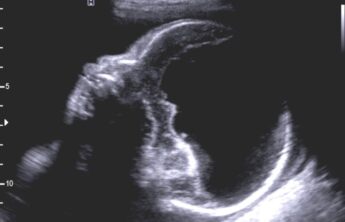

Holoprosencefalia alobar

Se caracteriza por marcados alteraciones en la línea media del encéfalo y/o malformaciones faciales.

Hallazgos radiológicos:

- Fusion completa de los hemisferios cerebrales

- Ausencia de la fisura interhemisferica y de la hoz cerebral

- Agenesia del cuerpo calloso y de la comisura anterior

- Holoventriculo, quiste dorsal

- Ausencia de septum pellucidum

- Los ganglios de la base de tálamos pueden estar diferenciados, funcionado o ausentes